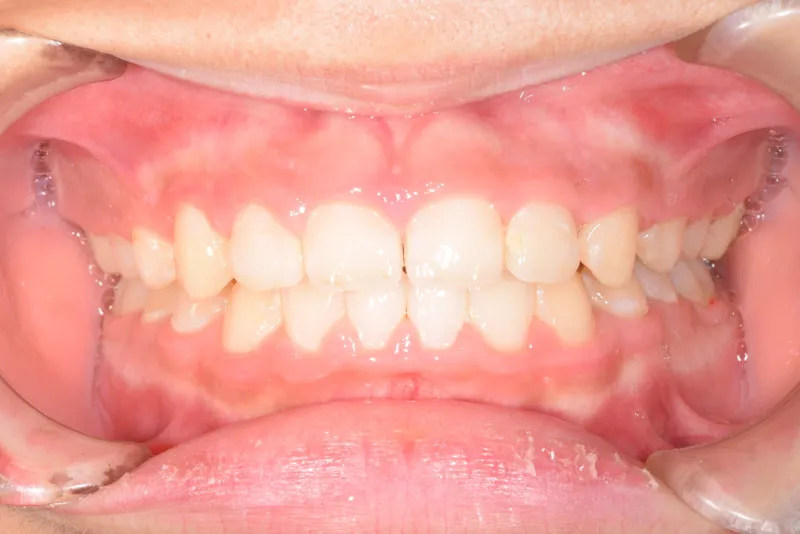

• 治療終了後

治療終了後

永久歯に生え変わってからはマルチブラケット装置を使用し、噛み合わせ・見た目をしっかり仕上げました。

治療回数42回、4年6ヶ月の治療期間で矯正治療を終了しました。

主訴が改善され、ご満足頂きました。